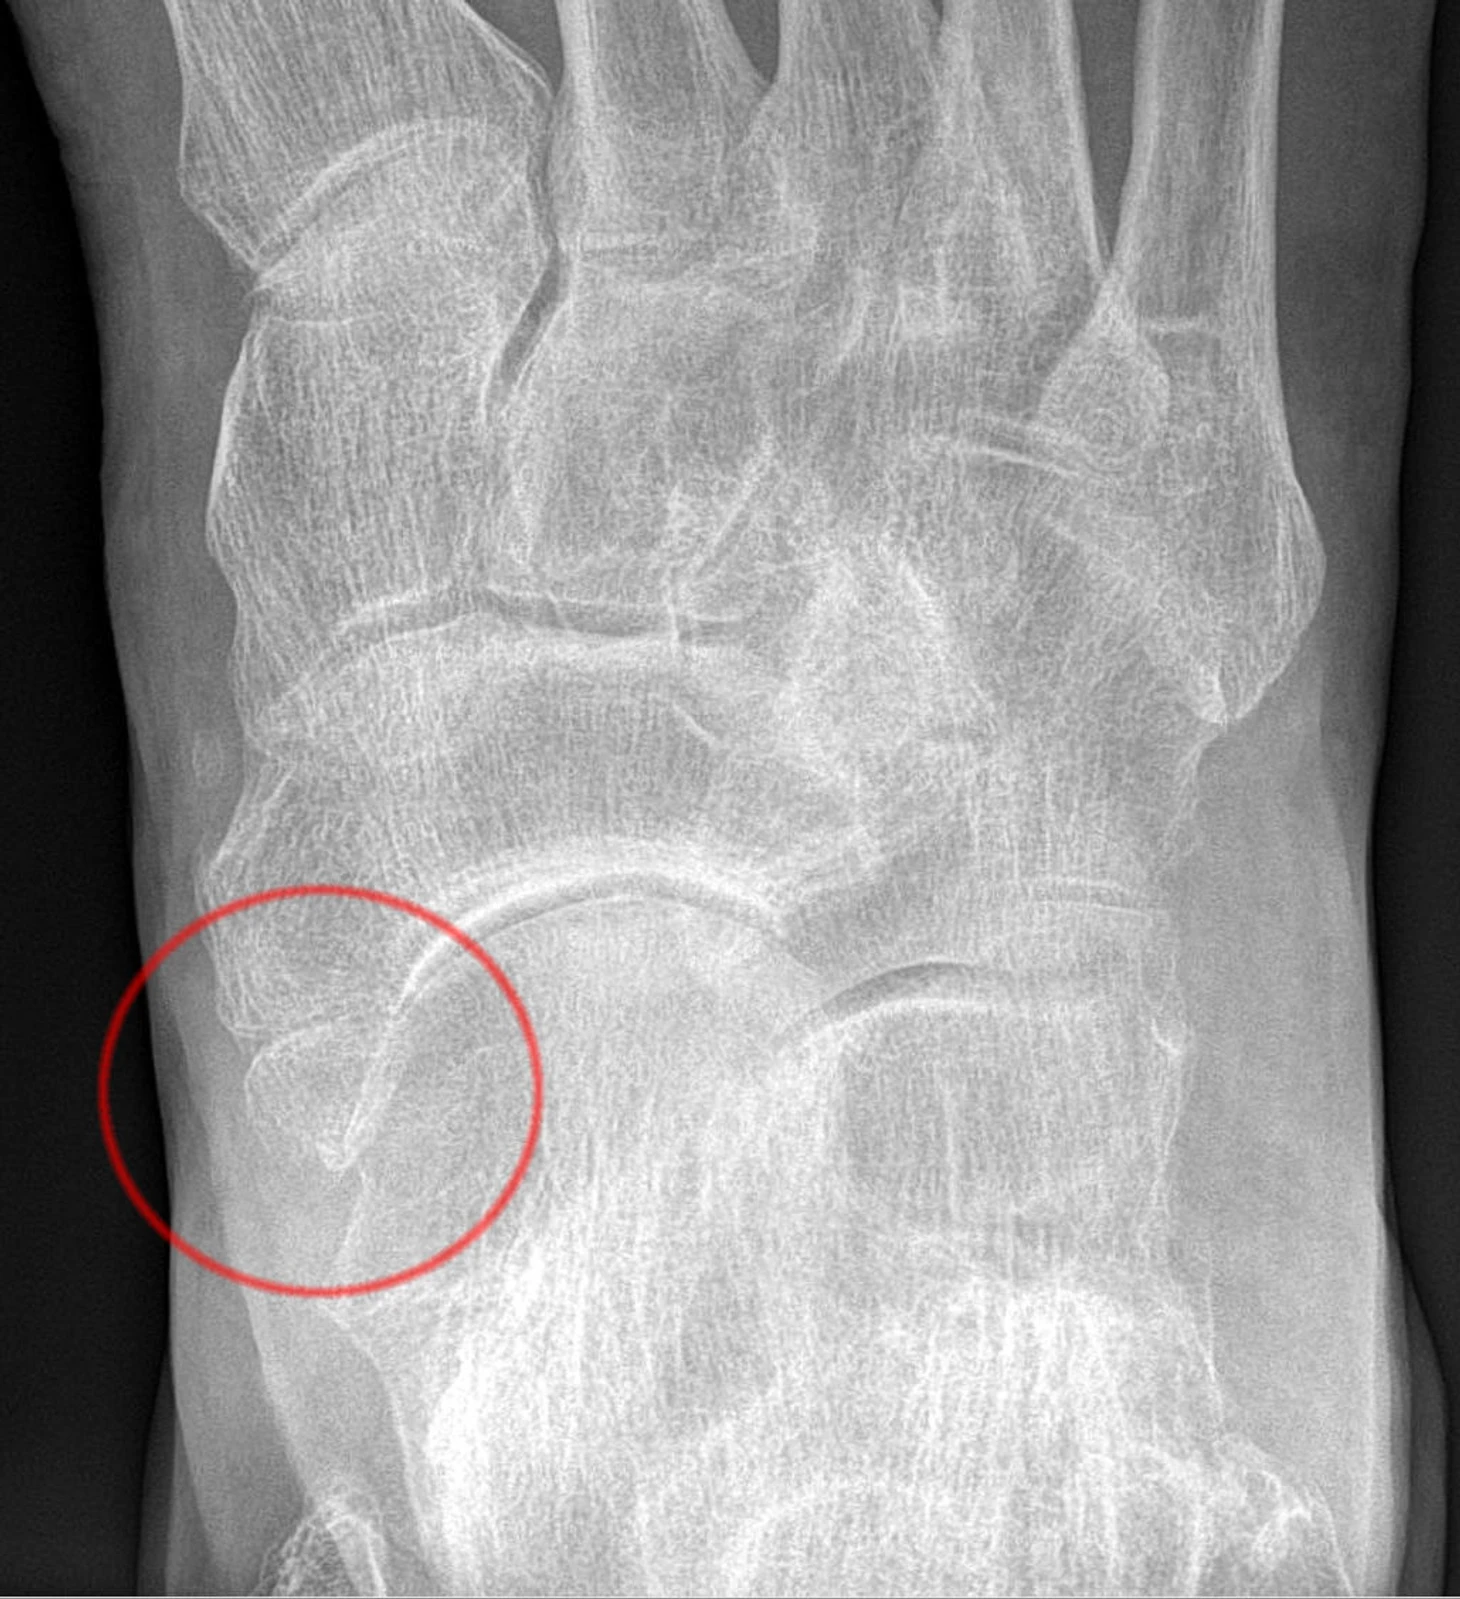

На снимке правая стопа, вид сверху. Красным кружком выделен фрагмент ладьевидной кости, как это может показаться на первый взгляд. Перелом! Но почему-то симптоматика не такая яркая, как при переломе, плюс, он почему-то не срастается. Что же не так? Это как раз добавочная ладьевидная кость (II типа), а линия между основной и добавочной костью – это не линия перелома, а синхондроз. И в «Лионе» поначалу попались в эту ловушку: Деян говорил о травме десятилетней давности, а в новостях о ней как раз двоякие формулировки — клуб вроде бы говорит, что перелом исключили, но в то же время все равно отправляет Ловрена на КТ (а не МРТ), которая наиболее чувствительна именно к повреждениям костной ткани и при помощи которой в том числе можно отличить синхондроз и добавочную кость от перелома.